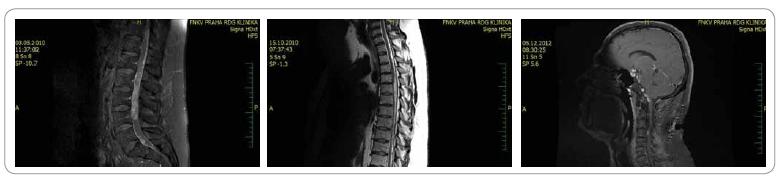

Muž, 38 let, zedník, aktivní sportovec, RA a OA negativní. V 5/2010 hospitalizován na neurologii pro progredující paraparézu DK se sfinkterovými obtížemi, KI 70 %. Na MRI L páteře zjištěna objemná Tu infiltrace L2-L4 a L5—S1. Provedena subtotální extirpace, histologicky oligodendrogliom G II. Pro nejednoznačný histologický popis provedeno druhé čtení, nález uzavřen jako atypický meningeom G II. Pooperačně těžká paraparéza DK, syndrom kaudy s inkontinencí, KI 40 %. Mezioborovým neuroonkologickým týmem indikována pooperační radioterapie Th12—S3, paliativní záměr při celkově špatném klinickém stavu, dále nedovyšetřován, odeslán k intenzivní rehabilitaci s časnou kontrolou. V 10/2010 zlepšení stavu pacienta, perzistence paraparézy DK, ale plně kontinentní, KI 70 %, kontrolní MRI L páteře bez rezidua či recidivy Tu. Dovyšetřena kraniospinální osa, kde zjištěno mnohočetné Tu postižení mozku a úseku Th a C páteře. Provedena subtotální resekce v rozsahu Th3—Th6, histologicky potvrzen atypický meningeom G II. Indikována pooperační radioterapie Th páteře, drobná ložiska mozku a C míchy k časné kontrole. Genetickým vyšetřením pacienta vyloučena přítomnost hereditárního nádorového syndromu. Při dalším sledování klinické lepšení, paraparéza DK do stoje s oporou, plná kontinence, KI 70 %, bez progrese na kontrolním MRI kraniospinální osy. V 7/2011 náhlá monoparéza PHK. Na MRI mozku progrese ložiska zadní jámy lební, ostatní MRI bez progrese. Tři ložiska zadní jámy lební ozářena Leksellovým gama nožem. Na kontrolním MRI mozku 3 měsíce po terapii parciální regrese, klinicky úplná úprava monoparézy PHK. V 4/2012 nové ložisko na MRI C míchy. Provedena subtotální resekce v rozsahu C2-4, histologicky atypický meningeom, ale s vyšší mitotickou aktivitou. Uvažováno o up-gradingu, odesláno ke druhému čtení, kde definitivně uzavřeno jako anaplastický astrocytom G III. Aplikována pooperační radioterapie C páteře. V 8/2012 mírná progrese drobného ložiskového postižení C míchy i oblasti mozkového kmene. Zahájena chemoterapie temozolomidem, která nyní v běhu. V 12/2012 po 3 cyklech chemoterapie stacionární klinický stav, na MRI parciální regrese, pokračováno v chemoterapii.